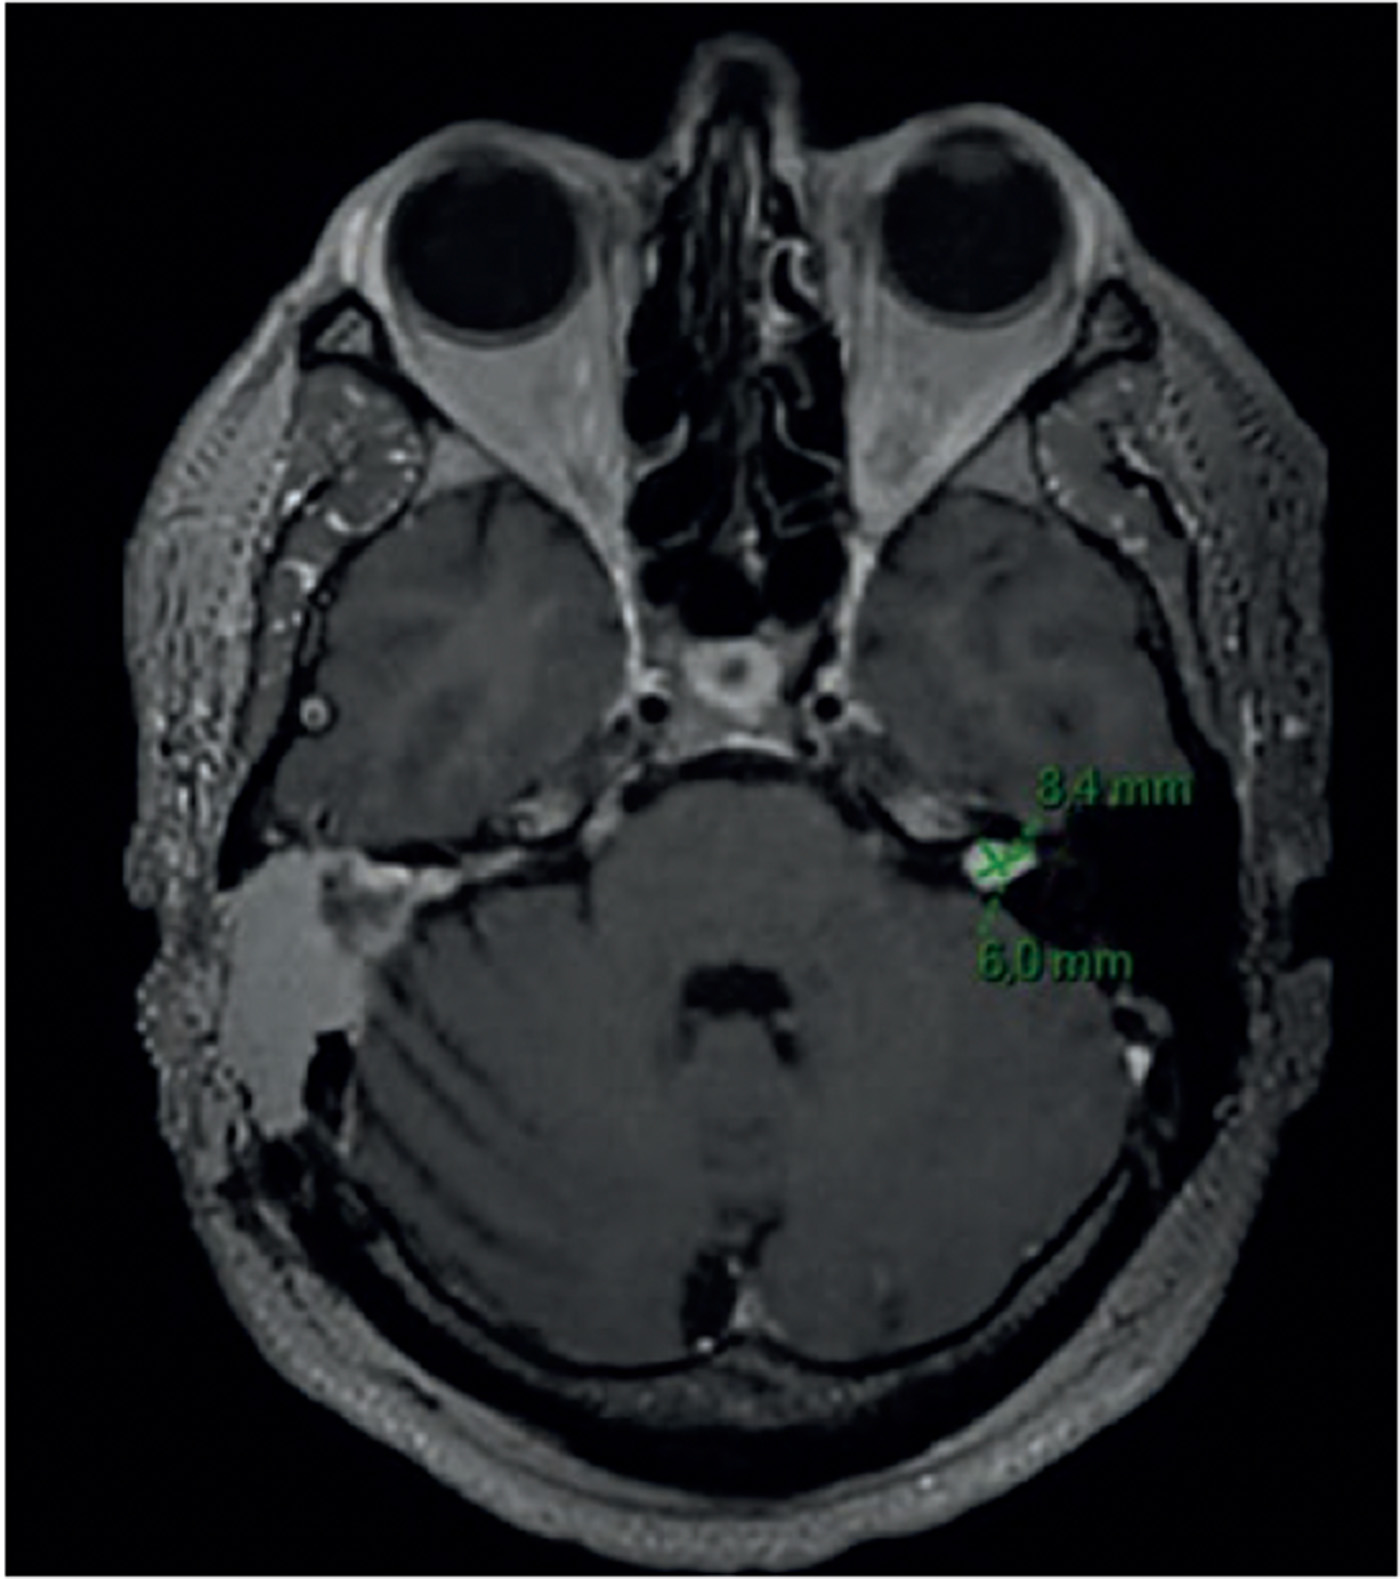

▶ IRM cérébrale et des rochers (janvier 2024, figure 3)

- Schwannome vestibulaire gauche de stade 1, atteignant le fond du CAE.

- Perméabilité de la cochlée conservée.